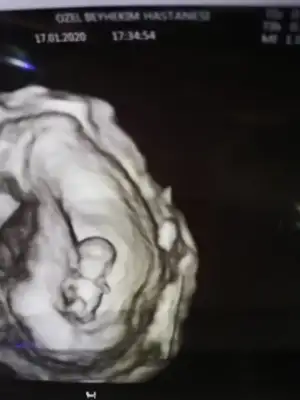

Maşşallah iyi hatırladınNubu paralel kafa yapısı erkek gibi demiştim hayırlısı olsun cnm

Maşşallah iyi hatırladınamin bakalım ama bence kız gbi

Kız gibi birde 11 yada 12 hafta usg paylaşırmısınızTeyzeleri bizde tahmin bekliyoruz 13+6 gunlukbizim grupta da tahmin edenler oldu bakalim siz ne diyeceksiniz